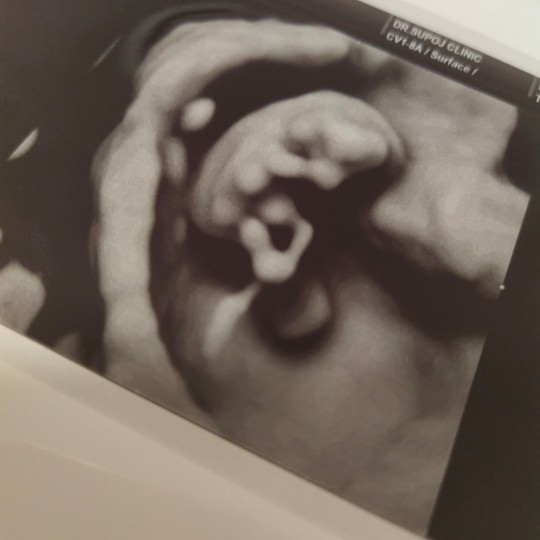

3 ธันวา ซาวด์ตอน9วีคค่ะ

3 ธันวา ค่าา ซาวส์ตอน 9w